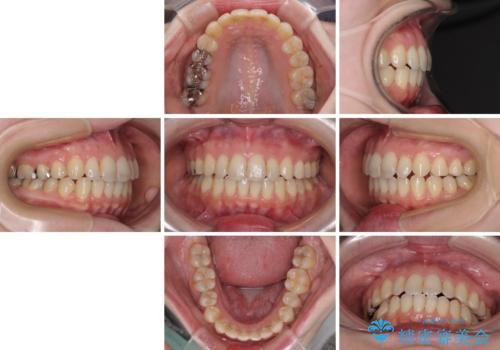

前歯のデコボコを改善 目立たないワイヤー矯正

- 2年6ヶ月

- 10-30回

- 前歯のデコボコを気にして来院された患者様です。

下顎が骨格的にずれており、上下正中を合わせることは難しいことが予想されたため、デコボコの解消を主目的として、ワイヤー矯正を行うこととしました。

治療途中で出産されたこともあり、当初予定よりも終了までに期間がかかってしまいました。

舌を前方に突出する癖があったため、上下前歯がなかなか接触しなかったことも治療期間が伸びた要因です。